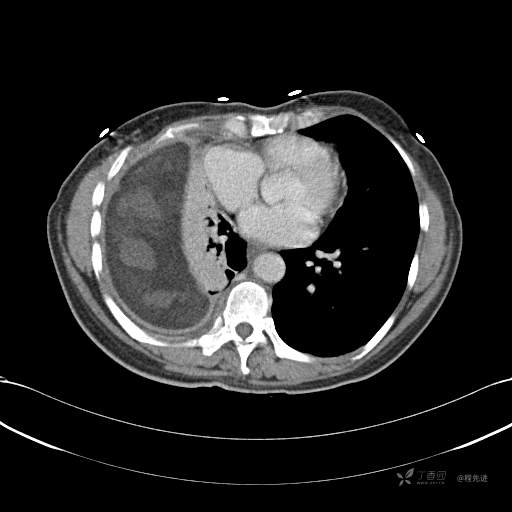

患者性别:女

患者年龄:51岁

简要病史:胸闷半年

肺淋巴管肌瘤病 (7)

乳糜胸 (8)